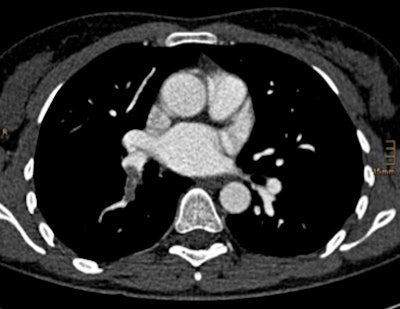

| Above, CTA showing an axial scan with an embolus at the right lower lobe. Below, corresponding coronal pulmonary blood volume map shows a perfusion defect of the right lower lobe. Images courtesy of Tobias de Zordo, MD, and Gudrun Feuchtner, MD. |